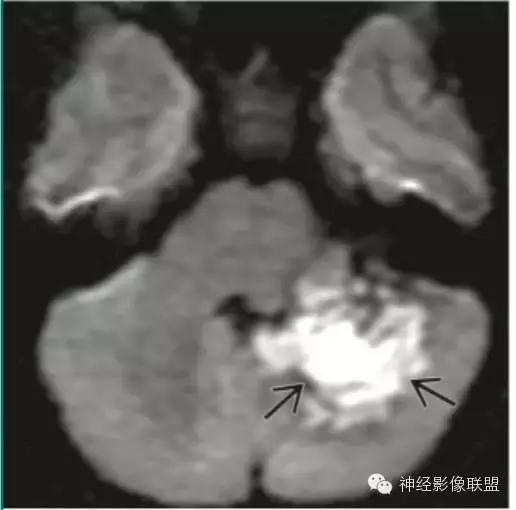

表皮样囊肿